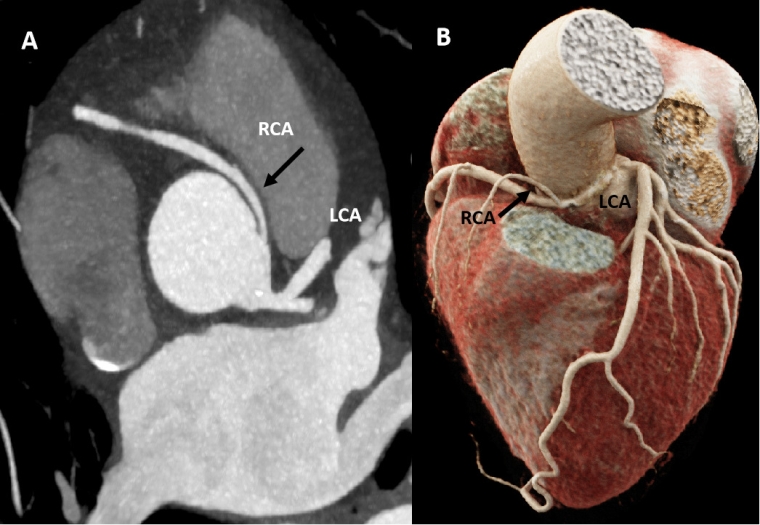

Figure 4. CCT of a 40-year-old male rugby player who suffered a syncope while exercising. The first ECG documented a transient third-degree atrioventricular block and the echocardiogram identified a possible anomalous coronary origin. A) CCT axial view with a maximum intensity projection, and B) CCT volumetric reconstruction. Both images confirmed an anomalous origin of the right coronary artery from the left sinus of Valsalva, with an acute angle origin, small intramural segment and interarterial course (high risk phenotype).

CCT: cardiac computed tomography; ECG: electrocardiogram